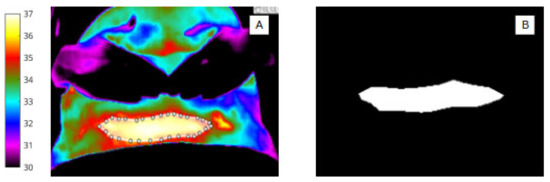

For abdomen (Figure 2A,B) and wound segmentation (Figure 3A,B), the respective regions were identified in infrared and the ROI was selected and cropped. With respect to the surgical site, ROI 2, determining the extent of the area, was often difficult to identify in infrared due to lack of clear anatomical landmarks. To help discern wound area from surrounding healthy skin, reference was made to the corresponding digital image.

Figure 3.

(A) Pixel-based wound segmentation (ROI 2). (B) Binary mask of wound region (ROI 2).